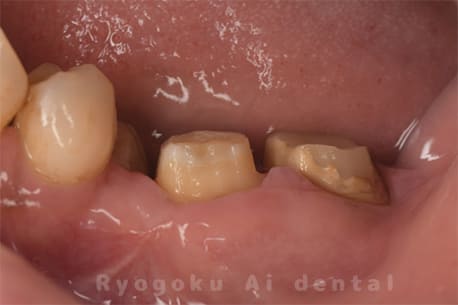

Case03

- 原因

- 急性化膿性根尖性歯周炎

- 治療期間

- 2ヶ月

- 治療内容

- マイクロエンド

- 治療費用

- 121,000円

黙っていても痛みが出るとのことで来院した患者様です。本治療は症状もあるため、抜髄治療をマイクロエンドで行いました。